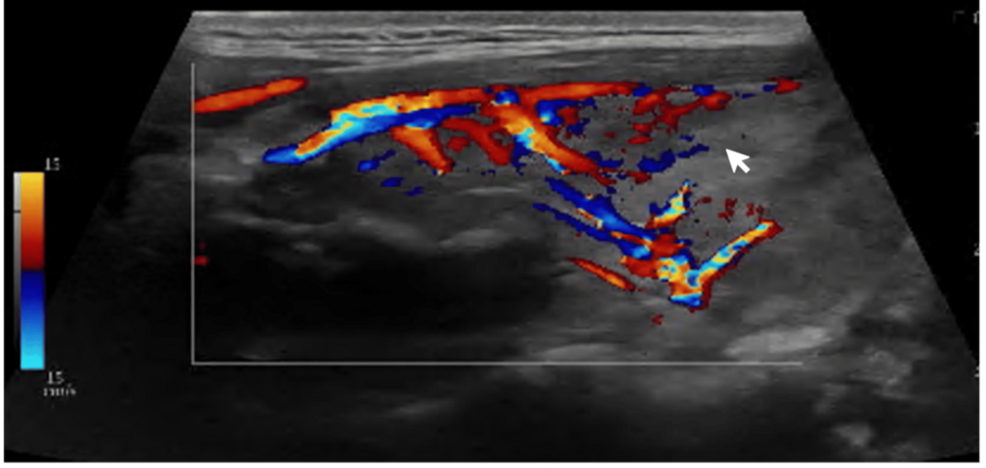

3. Thyroid Ultrasound: To assess thyroid size and morphology.